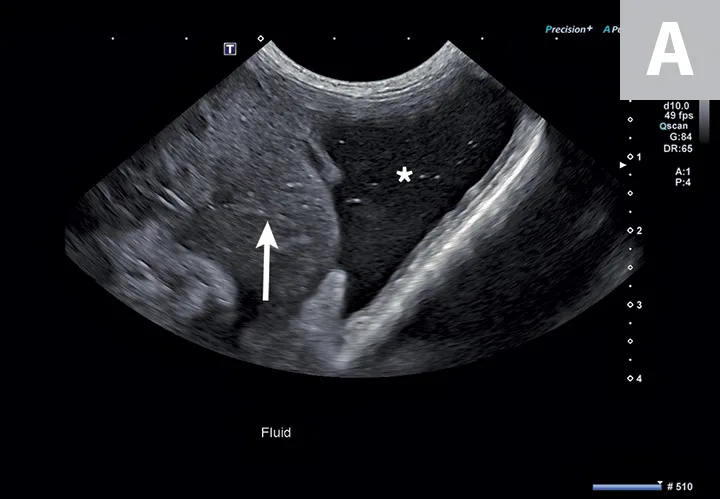

Two ultrasound images showing hypoechoic fluid adjacent to the spleen and to the heart.

FIGURE 2

Abdominal effusion (A; asterisk) adjacent to a normal spleen (arrow). Abdominal carcinomatosis with secondary neoplastic effusion was diagnosed. Left parasternal short-axis view of a heart with pericardial (B; asterisks) and pleural effusion (arrow).

The abdomen is most commonly evaluated with the patient in dorsal or lateral recumbency, but scanning the dependent portion with the patient in lateral recumbency can be helpful if only a small amount of effusion is present (see Suggested Reading).6,7 Evaluation for pleural effusion is performed with the patient standing or in ventral recumbency and should begin at the eighth to ninth intercostal space at the level of the costochondral junction. This space is also recommended when thoracocentesis is used in these patients.8 Evaluation for pericardial effusion in the right third to fifth intercostal space at the level of the costochondral junction provides the best acoustic window to the heart.5

Cavitary effusion is normally anechoic on ultrasound but can differ based on fluid type.6 Echogenicity and cytologic classification of effusion is based on cellular and protein content, increasing in echogenicity from pure transudate (anechoic) to modified transudate (variably echoic) and exudate (hyperechoic)6,9; however, the echogenicity of cavitary fluid can vary; thus, fluid analysis is required to confirm the exact nature of the fluid.